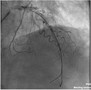

元柏民教授:STEMI静脉溶栓的地位与时机

2015年6月12日至14日,第四届中国基层心血管病大会在美丽的“狮城”河北沧州成功举办。河北省心血管病分会常委、沧州市中心医院的元柏民教授在大会上做了题为“STEMI静